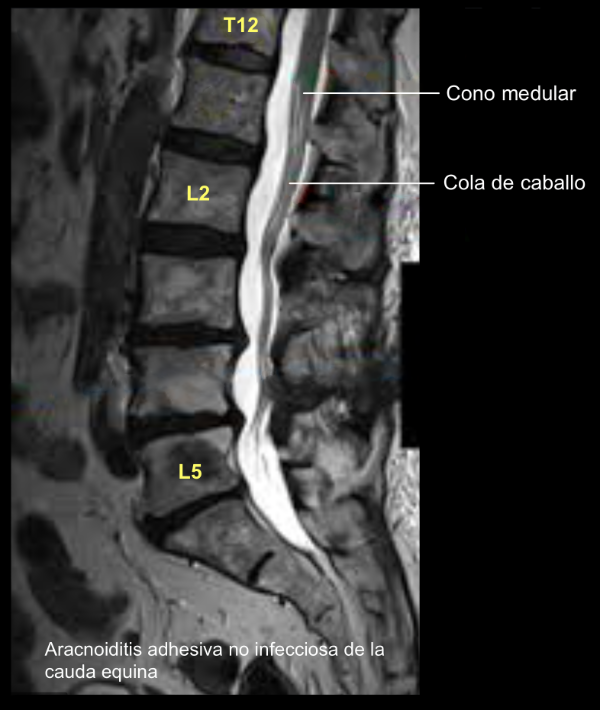

Síndrome de cauda equina

Se informó de 32 pacientes con síndrome de cauda equina y paraparesia en cuatro pacientes. La condición fue permanente en todos los pacientes. En 8 pacientes se utilizó lidocaína 5% hiperbárica, bupivacaína 0.5% en 11 casos (6 hiperbárica, 5 isobárica), y en un caso se utilizó una mezcla de ambos fármacos. Un paciente recibió mepivacaína a través de un catéter espinal. Se diagnosticó aracnoiditis tras bloqueo espinal en dos pacientes varones.Se encontró meningitis en 29 casos: 12 mujeres (32-79 años, mediana 62) y 17 hombres (21-74 años; mediana 62). El bloqueo espinal precedió a la meningitis en 24 casos, incluido un caso de bloqueo mixto. En un caso, la meningitis se produjo después de un bloqueo epidural y una mielografía. Por lo tanto, se produjo meningitis después de una perforación documentada de la duramadre en 25 de 29 casos. La incidencia global de meningitis después del bloqueo espinal fue de 1:53,000; sin embargo, en un departamento de anestesiología la incidencia fue de 1:3,000 como resultado de la agrupación de cuatro casos. En los casos que ocurrieron después de un bloqueo espinal con una sola dosis, todos los pacientes excepto dos estaban sanos. De estos, un paciente era diabético y un segundo paciente estaba bajo terapia de sustitución de esteroides para enfermedad de Addison. Tres casos se presentaron después del tratamiento por dolor crónico con catéter espinal permanente. Un paciente era diabético y otro paciente con cáncer diseminado estaba en tratamiento con esteroides sistémicos.